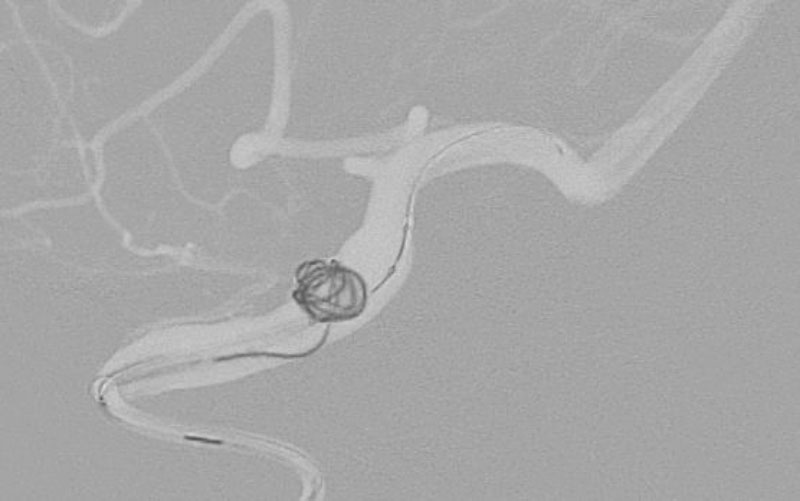

No.1627 手術中